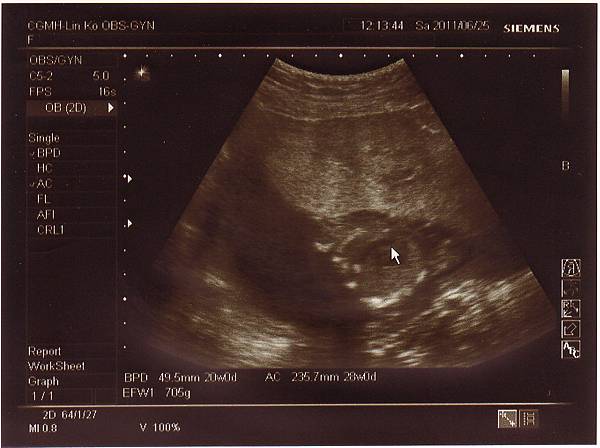

2011.06.25 當天先去超音波室做了仔細的超音波檢查,

檢查心臟.是否兔唇.手腳.肺動脈....等等,

一切都非常正常,也確定是個兔女郎!